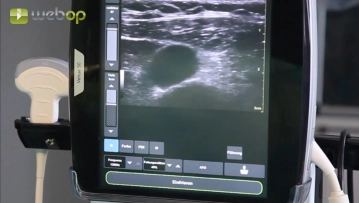

Nach Hautdesinfektion und steriler Abdeckung erfolgt die Duplex-Sonographie zwecks Lokalisation der Vena jugularis interna. Im Clip nicht dargestellt ist die Lokalanästhesie, welche die gewählte Halsseite, den gesamten Subkutankanal und die spätere perkutane Austrittsstelle des Katheters infraclavikulär umfasst. In der Regel werden 10-15 ml Lokalanästhesitkum benötigt (z. B. Xylonest® 1%ig).

Duplex-Sonographie der Vena jugularis interna rechts, Lokalanästhesie